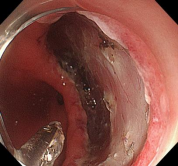

消化道早癌的病例展示(经内镜手术或活检证实):

直肠巨大侧向发育型肿瘤,内镜下完整切除(ESD),术后病理证实粘膜内癌,不需追加治疗,达到治愈目的,保留正常器官,避免外科手术。